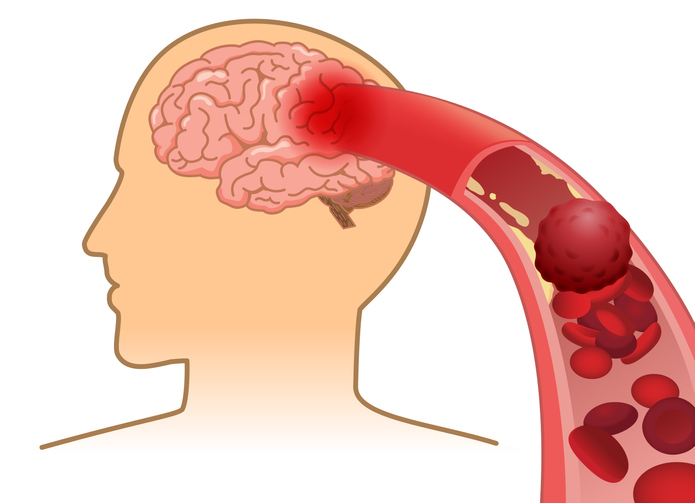

뇌졸중은 뇌 일부분에 혈액을 공급하는 혈관이 막히거나 터지면서 뇌가 손상돼 신경학적 이상이 나타나는 병입니다. 밤과 낮 그리고 실내외 온도 차가 계절에는 혈압 상승과 혈관 과부하로 심뇌혈관 질환 발병 우려가 매우 높습니다.

뇌에 혈액을 공급하는 혈관이 막히게 되면 뇌의 일부가 손상되는 ‘뇌경색 증상’, 뇌혈관이 터져 주변 뇌가 손상되는 ‘뇌출혈 증상’이 있습니다. 두 질병 모두 사망에 이르거나 뇌손상으로 인한 후유증이나 신체장애를 남길 수 있는 위험한 질환입니다.